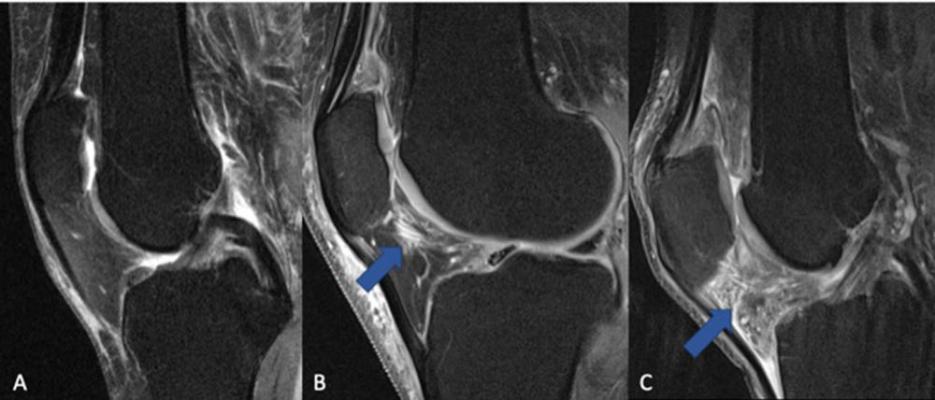

“To date, no curative therapy has been approved to cure or reduce the progression of knee osteoarthritis,” said the study’s lead author, Johanna Luitjens, M.D., postdoctoral scholar in the Department of Radiology and Biomedical Imaging at the University of California, San Francisco. “NSAIDs are frequently used to treat pain, but it is still an open discussion of how NSAID use influences outcomes for osteoarthritis patients. In particular, the impact of NSAIDs on synovitis, or the inflammation of the membrane lining the joint, has never been analyzed using MRI-based structural biomarkers.”

Dr. Luitjens and colleagues set out to analyze the association between NSAID use and synovitis in patients with osteoarthritis of the knee and to assess how treatment with NSAIDs affects joint structure over time.

“Synovitis mediates development and progression of osteoarthritis and may be a therapeutic target,” Dr. Luitjens said. “Therefore, the goal of our study was to analyze whether NSAID treatment influences the development or progression of synovitis and to investigate whether cartilage imaging biomarkers, which reflect changes in osteoarthritis, are impacted by NSAID treatment.”

For the study, 277 participants from the Osteoarthritis Initiative cohort with moderate to severe osteoarthritis and sustained NSAID treatment for at least one year between baseline and four-year follow-up were included in the study and compared with a group of 793 control participants who were not treated with NSAIDs. All participants underwent 3T MRI of the knee initially and after four years. Images were scored for biomarkers of inflammation.

Cartilage thickness, composition and other MRI measurements served as noninvasive biomarkers for evaluating arthritis progression.

The results showed no long-term benefit of NSAID use. Joint inflammation and cartilage quality were worse at baseline in the participants taking NSAIDs, compared to the control group, and worsened at four-year follow-up.